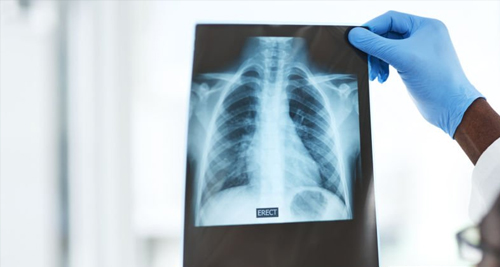

Doctor holding up chest X-ray to diagnose rib fracture

A medical professional examines a chest X-ray to confirm the presence of a broken rib and assess the extent of the injury.

Standard X-rays are commonly used to confirm rib fractures. However, small cracks may not always appear clearly on X-rays. In cases of persistent pain with a negative X-ray. A CT scan is often more accurate and can identify hidden fractures and associated injuries.

A chest X-ray may also reveal complications such as a collapsed lung, haemothorax (blood in the chest cavity), or fluid build-up. In patients with breathing difficulty or signs of internal injury, imaging of the abdomen and lungs may be included.